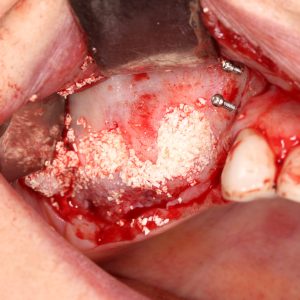

Sinus lift is usually performed under local anesthesia. After carefully lifting the sinus membrane, a bone graft is placed in this space. The graft can be made of synthetic materials or bone tissue taken from the patient's own body. During the healing process, new bone tissue forms in the area where the graft is placed, and this process usually takes 4-9 months. When sufficient bone volume is created, implants can be applied.

Under local anesthesia, the sinus membrane is carefully lifted and a bone graft is placed.

It takes 4-9 months for the placed bone graft to ossify.